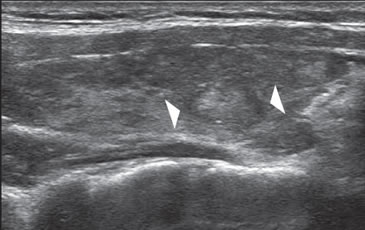

Otro tipo de lesión que se asocia a alta probabilidad de benignidad es un nódulo hiperecogénico8, parcialmente encapsulado, habitualmente un pseudo nódulo, que aparece en una glándula con cambios morfológicos por tiroiditis de Hashimoto (Figura 22). Hay que tener presente que la concomitancia de tiroiditis de Hashimoto y bocio nodular no es un argumento a favor de benignidad, de manera que si el nódulo muestra características sospechosas o ha crecido, debe considerarse el realizar una PAAF12. La tiroiditis de Hashimoto puede presentarse con un patrón benigno clásico, de múltiples pequeños pseudo nódulos, relativamente hipoecogénicos, uniformemente distribuidos (Figura 23a y b), en una glándula aumentada de volumen, de superficie lobulada, hipoecogénica e hipervasularizada. Es frecuente encontrar adenopatías infratiroideas bilaterales de aspecto muy característico.

Figura 23. a) y b) Aspecto típico de tiroiditis de Hashimoto con múltiples pseudo-nódulos hipoecogénicos (flecha) y aumento de la vascularización

del tejido.